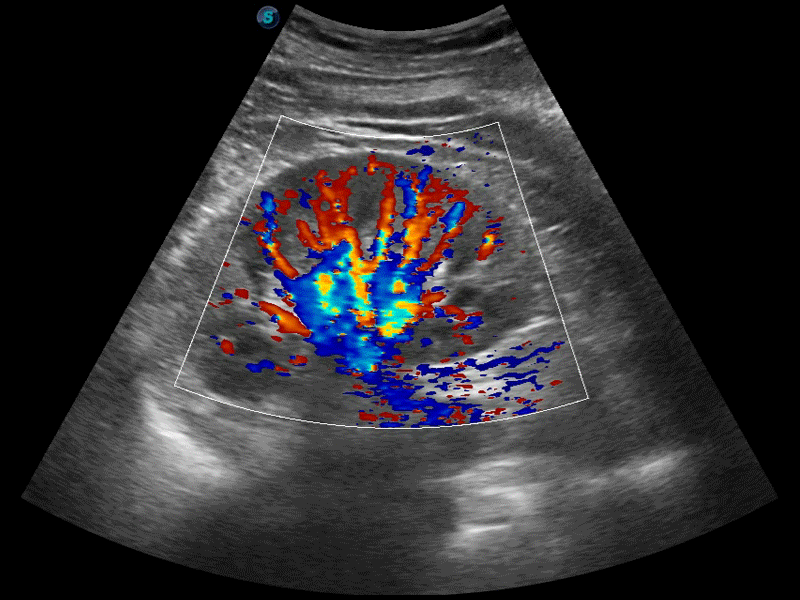

高分辨率血流成像技术提高了对低速血流信号的检测能力。在提高空间分辨率的同时,也克服了血流外溢现象,为用户提供更加真实的血流动力学信息。